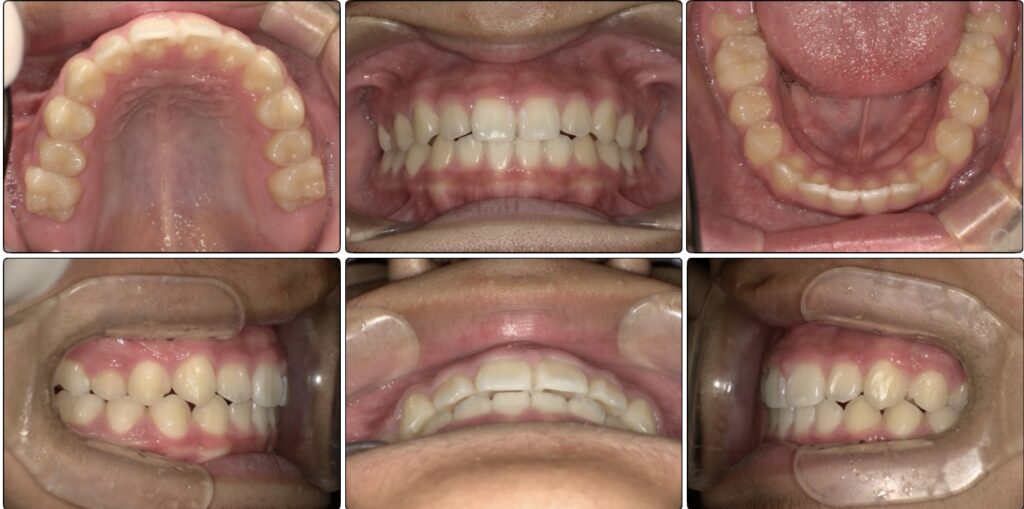

治療前 / 現在

治療開始時

現在